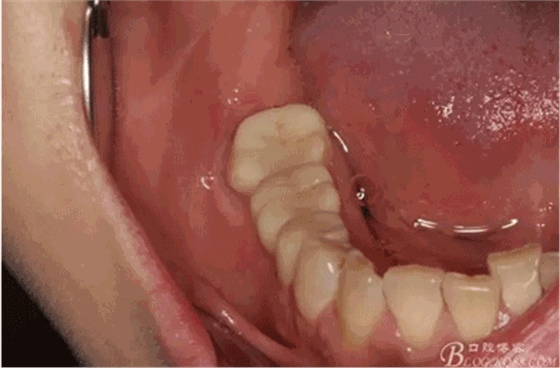

圖3.患者的口內(nèi)照片:47-45全瓷橋修復(fù),頰側(cè)牙齦輕度紅腫。